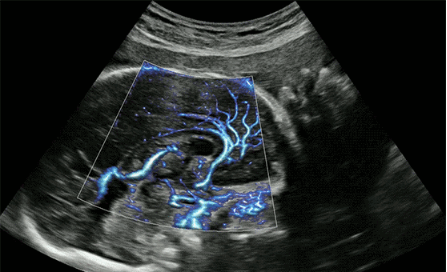

CrystalLive?是三星最新的超聲成像引擎,同時(shí)增強(qiáng)了2D圖像處理能力、3D渲染能力和彩色信號(hào)處理能力,能夠在復(fù)雜情況下提供出色的圖像性能,具備檢測外周血管、微循環(huán)血流的能力。

2D成像方面,Hera i10集成了包括ShadowHDR?、HQ-Vision?、ClearVision等多項(xiàng)具有三星“血統(tǒng)”的技術(shù),加強(qiáng)了圖像的陰影抑制、減少偽影、緩和模糊區(qū)。